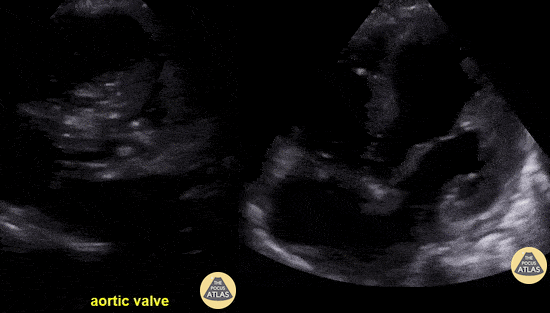

A 35-year-old with history of a "heart problem" presented for concern of COVID-19. He was found to be in wide complex tachycardia with hemodynamic instability (MAP 50) with associated findings of crushing chest pain and diaphoresis. RUSH demonstrated severely reduced EF, a tricuspid valve vegetation, and aortic valve vegetation complicated by aortic root abscess. Seen here is a parasternal short axis view (on the left) demonstrating an almost entirely occluded aortic valve and outflow tract. The apical four chamber view (on the right) demonstrates both a tricuspid valve vegetation as well as this patient’s severely reduced LVEF. Gregory Wiener, MD. Denver Health Residency in Emergency Medicine @DenverEMed